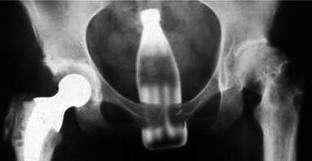

da der anus/enddarm dehnbar ist wirst du irgendwann auch nix mehr wirklich spüren wenn du ne colaflasche drin hast.deshalb werden die spielzeuge irgendwann immer größer

bitte keine colaflasche, die notärzte sind deshalb schon oft genug im einsatz

kommt drauf an, wie rum die colaflasche ;-)

na mit dem boden zuerst...hier sind doch keine weicheier

aber bitte wieder rauslassen,da ist pfand drauf

ja wenn schon dann bitte die 3 liter cola flasche aus der postenbörse...die ist gar pfandfrei!